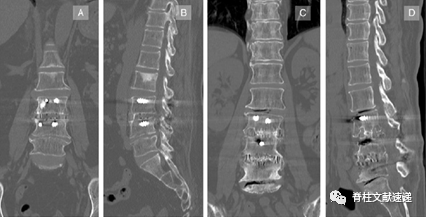

图1.通过透视的正位(A)和侧位(B)X线进行“造影剂充填技术”,以确保椎间椎间盘切除术的有效性,并检查术中终板有无损伤。